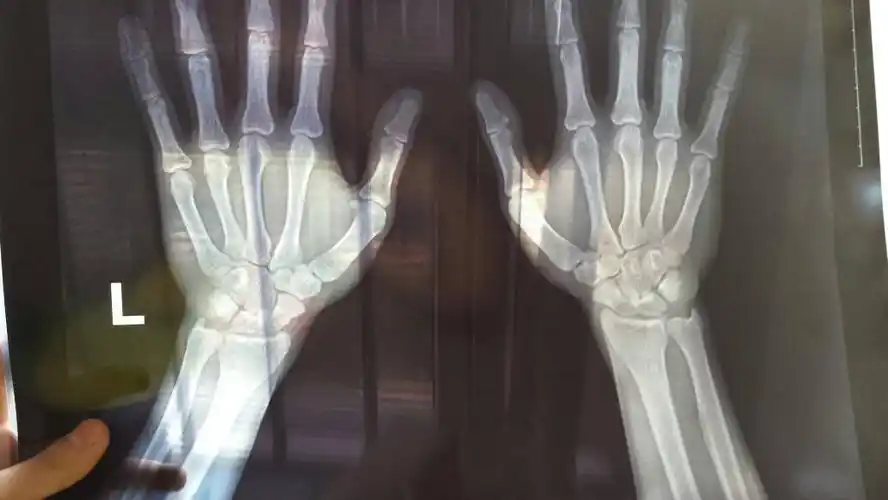

今天去拍了手骨的片子看看骨骺线闭合没,还能长多高,懂的人给我看看吧

骨骺线已近闭合

医生请帮忙认真看下骨骺线闭合没,非常感谢,顺便问一下,要怎么看?